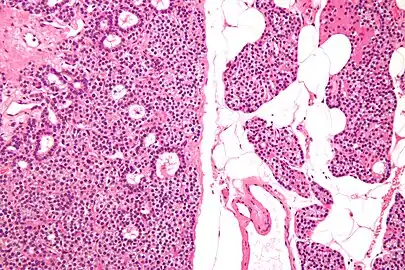

- Micrograph of a parathyroid adenoma (left) and normal parathyroid gland (right). H&E stain.

- Normal parathyroid gland with prominent adipose tissue is seen on the right of the image.-High magnification